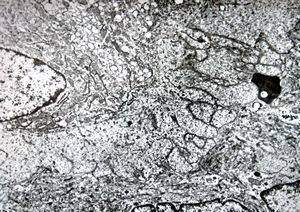

M,19y. | osteoid - chondrosarcoma - jaw

M,19y. | osteocyte - chondrosarcoma - jaw